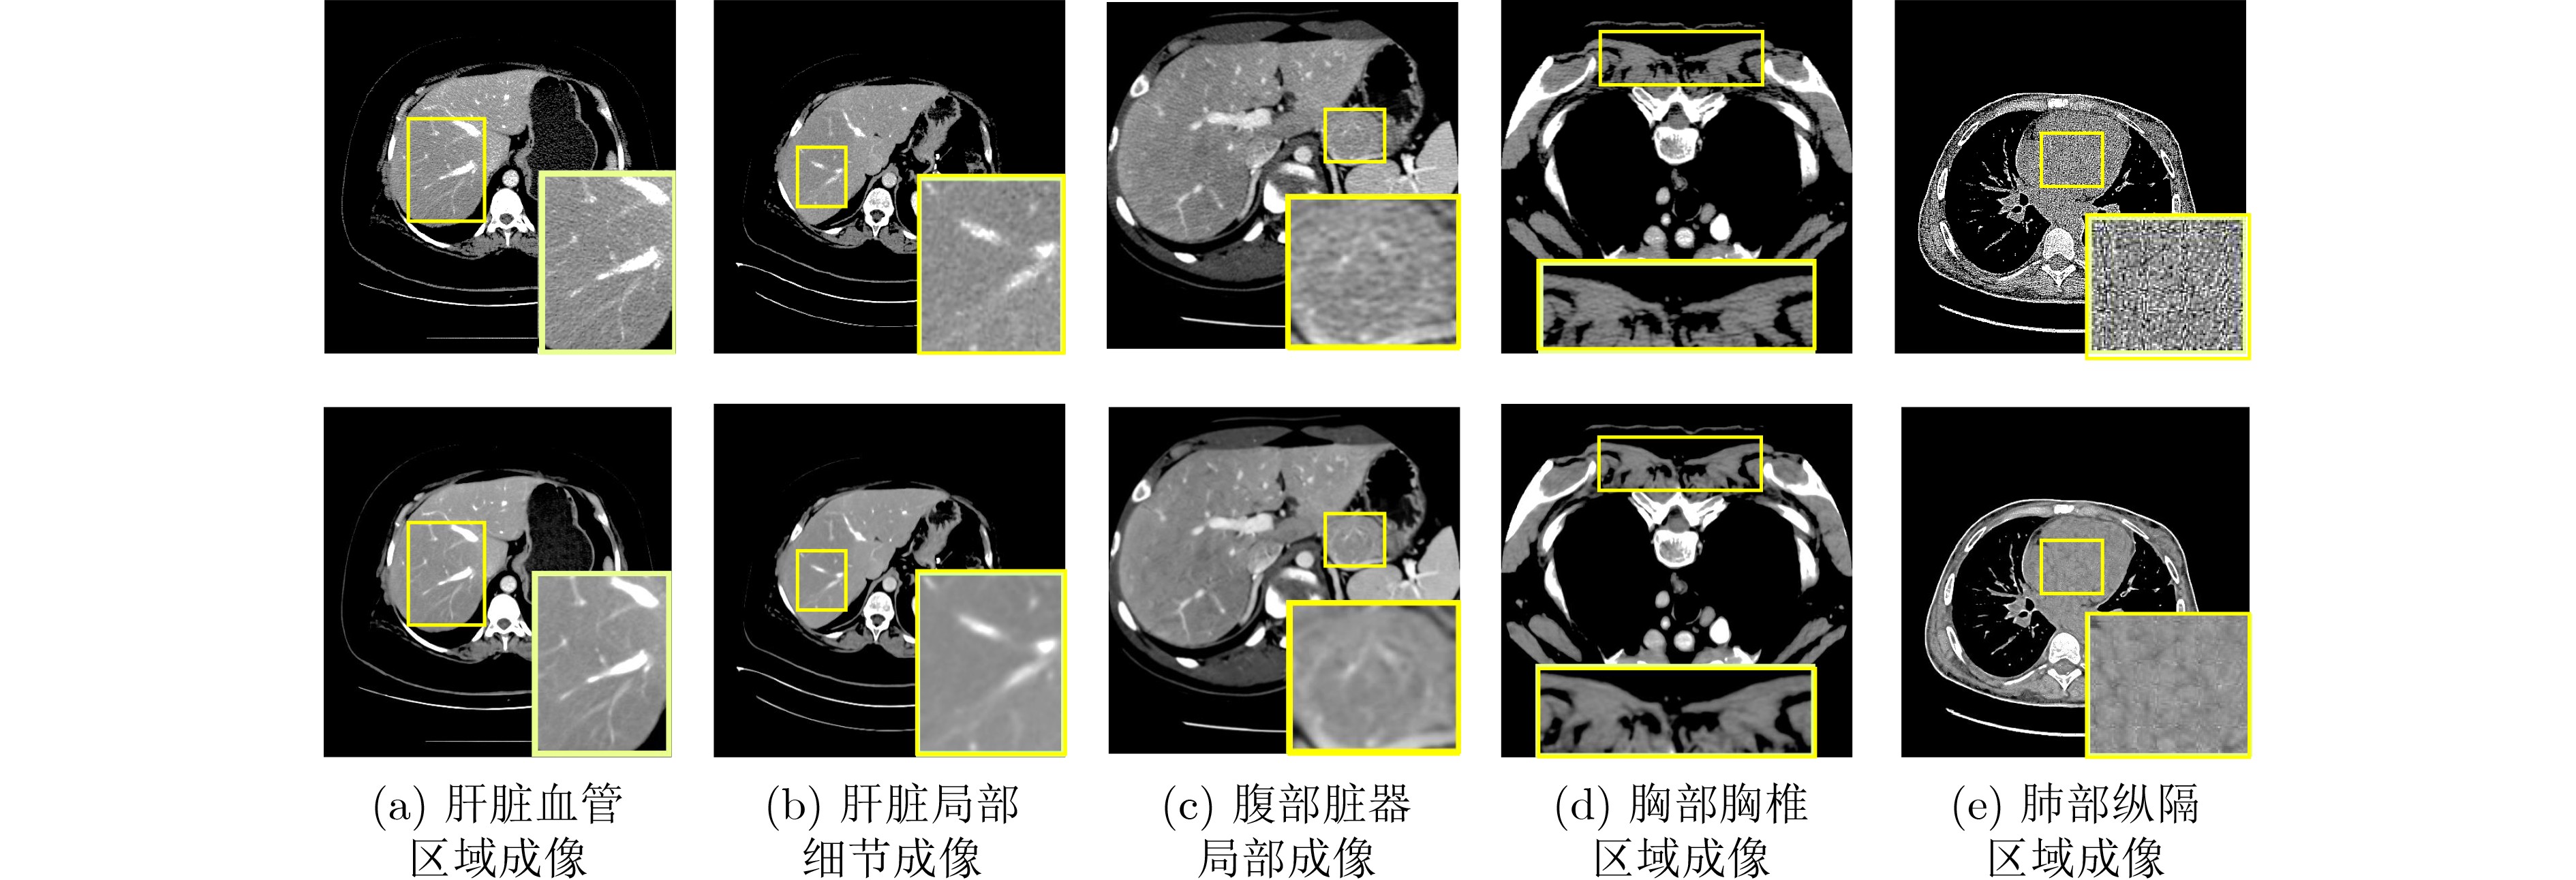

•   Objective  Low-Dose Computed Tomography (LDCT) reduces patient radiation exposure but introduces substantial noise and artifacts into reconstructed images. Convolutional Neural Network (CNN)-based denoising approaches are limited by local receptive fields, which restrict their abilities to capture long-range dependencies. Transformer-based methods alleviate this limitation but incur quadratic computational complexity relative to image size. In contrast, State Space Model (SSM)–based Mamba frameworks achieve linear complexity for long-range interactions. However, existing Mamba-based methods often suffer from information loss and insufficient noise suppression. To address these limitations, we propose the Wave-MambaCT model.  Methods  The proposed Wave-MambaCT model adopts a multi-scale framework that integrates Discrete Wavelet Transform (DWT) with a Mamba module based on the SSM. First, DWT performs a two-level decomposition of the LDCT image, decoupling noise from Low-Frequency (LF) content. This design directs denoising primarily toward the High-Frequency (HF) components, facilitating noise suppression while preserving structural information. Second, a residual module combined with a Spatial-Channel Mamba (SCM) module extracts both local and global features from LF and HF bands at different scales. The noise-free LF features are then used to correct and enhance the corresponding HF features through an attention-based Cross-Frequency Mamba (CFM) module. Finally, inverse wavelet transform is applied in stages to progressively reconstruct the image. To further improve denoising performance and network stability, multiple loss functions are employed, including L1 loss, wavelet-domain LF loss, and adversarial loss for HF components.  Results and Discussions  Extensive experiments on the simulated Mayo Clinic datasets, the real Piglet datasets, and the hospital clinical dataset DeepLesion show that Wave-MambaCT provides superior denoising performance and generalization. On the Mayo dataset, a PSNR of 31.6528 is achieved, which is higher than that of the suboptimal method DenoMamba (PSNR 31.4219), while MSE is reduced to 0.00074 and SSIM and VIF are improved to 0.8851 and 0.4629, respectively (Table 1). Visual results (Figs. 46) demonstrate that edges and fine details such as abdominal textures and lesion contours are preserved, with minimal blurring or residual artifacts compared with competing methods. Computational efficiency analysis (Table 2) indicates that Wave-MambaCT maintains low FLOPs (17.2135 G) and parameters (5.3913 M). FLOPs are lower than those of all networks except RED-CNN, and the parameter count is higher only than those of RED-CNN and CTformer. During training, 4.12 minutes per epoch are required, longer only than RED-CNN. During testing, 0.1463 seconds are required per image, which is at a medium level among the compared methods. Generalization tests on the Piglet datasets (Figs. 7, 8, Tables 3, 4) and DeepLesion (Fig. 9) further confirm the robustness and generalization capacity of Wave-MambaCT.In the proposed design, HF sub-bands are grouped, and noise-free LF information is used to correct and guide their recovery. This strategy is based on two considerations. First, it reduces network complexity and parameter count. Second, although the sub-bands correspond to HF information in different orientations, they are correlated and complementary as components of the same image. Joint processing enhances the representation of HF content, whereas processing them separately would require a multi-branch architecture, inevitably increasing complexity and parameters. Future work will explore approaches to reduce complexity and parameters when processing HF sub-bands individually, while strengthening their correlations to improve recovery. For structural simplicity, SCM is applied to both HF and LF feature extraction. However, redundancy exists when extracting LF features, and future studies will explore the use of different Mamba modules for HF and LF features to further optimize computational efficiency.  Conclusions  Wave-MambaCT integrates DWT for multi-scale decomposition, a residual module for local feature extraction, and an SCM module for efficient global dependency modeling to address the denoising challenges of LDCT images. By decoupling noise from LF content through DWT, the model enables targeted noise removal in the HF domain, facilitating effective noise suppression. The designed RSCM, composed of residual blocks and SCM modules, captures fine-grained textures and long-range interactions, enhancing the extraction of both local and global information. In parallel, the Cross-band Enhancement Module (CEM) employs noise-free LF features to refine HF components through attention-based CFM, ensuring structural consistency across scales. Ablation studies (Table 5) confirm the essential contributions of both SCM and CEM modules to maintaining high performance. Importantly, the model’s staged denoising strategy achieves a favorable balance between noise reduction and structural preservation, yielding robustness to varying radiation doses and complex noise distributions.